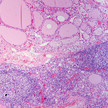

Schilddrüsen-Erkrankungen Hashimoto früher erkennen

Antriebslosigkeit, Nackenschmerzen und Muskelverhärtungen sind Symptome, die auf Hashimoto hinweisen können. Bei Kindern wird die chronische Entzündung der... Mehr»